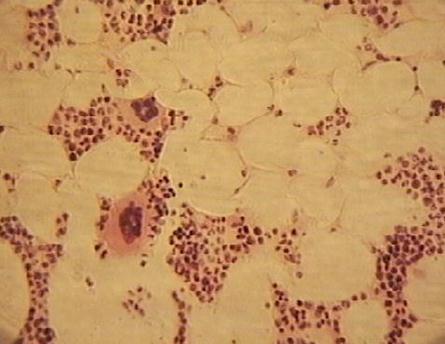

Фото 2.1.1. Красный костный мозг. Срез.

Гем.-Эоз. Малое увеличение. (Ув.10х7)

Срез красного костного мозга выглядит как скопление множества клеток с синими ядрами. Это гемопоэтические клетки разных стадий развития и зрелые форменные элементы крови. В отличие от мазка красного костного мозга, на его срезе отдельные виды клеток практически невозможно отличить друг от друга. Исключение составляют гигантские клетки костного мозга – мегакариоциты. В красном костном мозге всегда присутствуют жировые клетки. На препарате можно встретить артерии и синусоидные капилляры, заполненные эритроцитами.

а) рассмотреть гемопоэтическую ткань. Клетки миелоидной ткани мелкие, округлые, ядра окрашены базофильно.

б) найти адипоциты. Адипоциты (жировые клетки) - крупные, округлой формы, расположены обычно группами.

а) найти мегакариоцит. Гигантские клетки костного мозга мельче адипоцитов, имеют оксифильно окрашенную цитоплазму и базофильно окрашенное дольчатое ядро.

б) найти ретикулярную клетку. Ретикулярные клетки стромы костного мозга легче всего найти между прилегающими друг к другу клетками жировой ткани. Ретикулярные клетки мелкие, имеют отростки. Ядро округлое, цитоплазма слабо оксифильно окрашена.